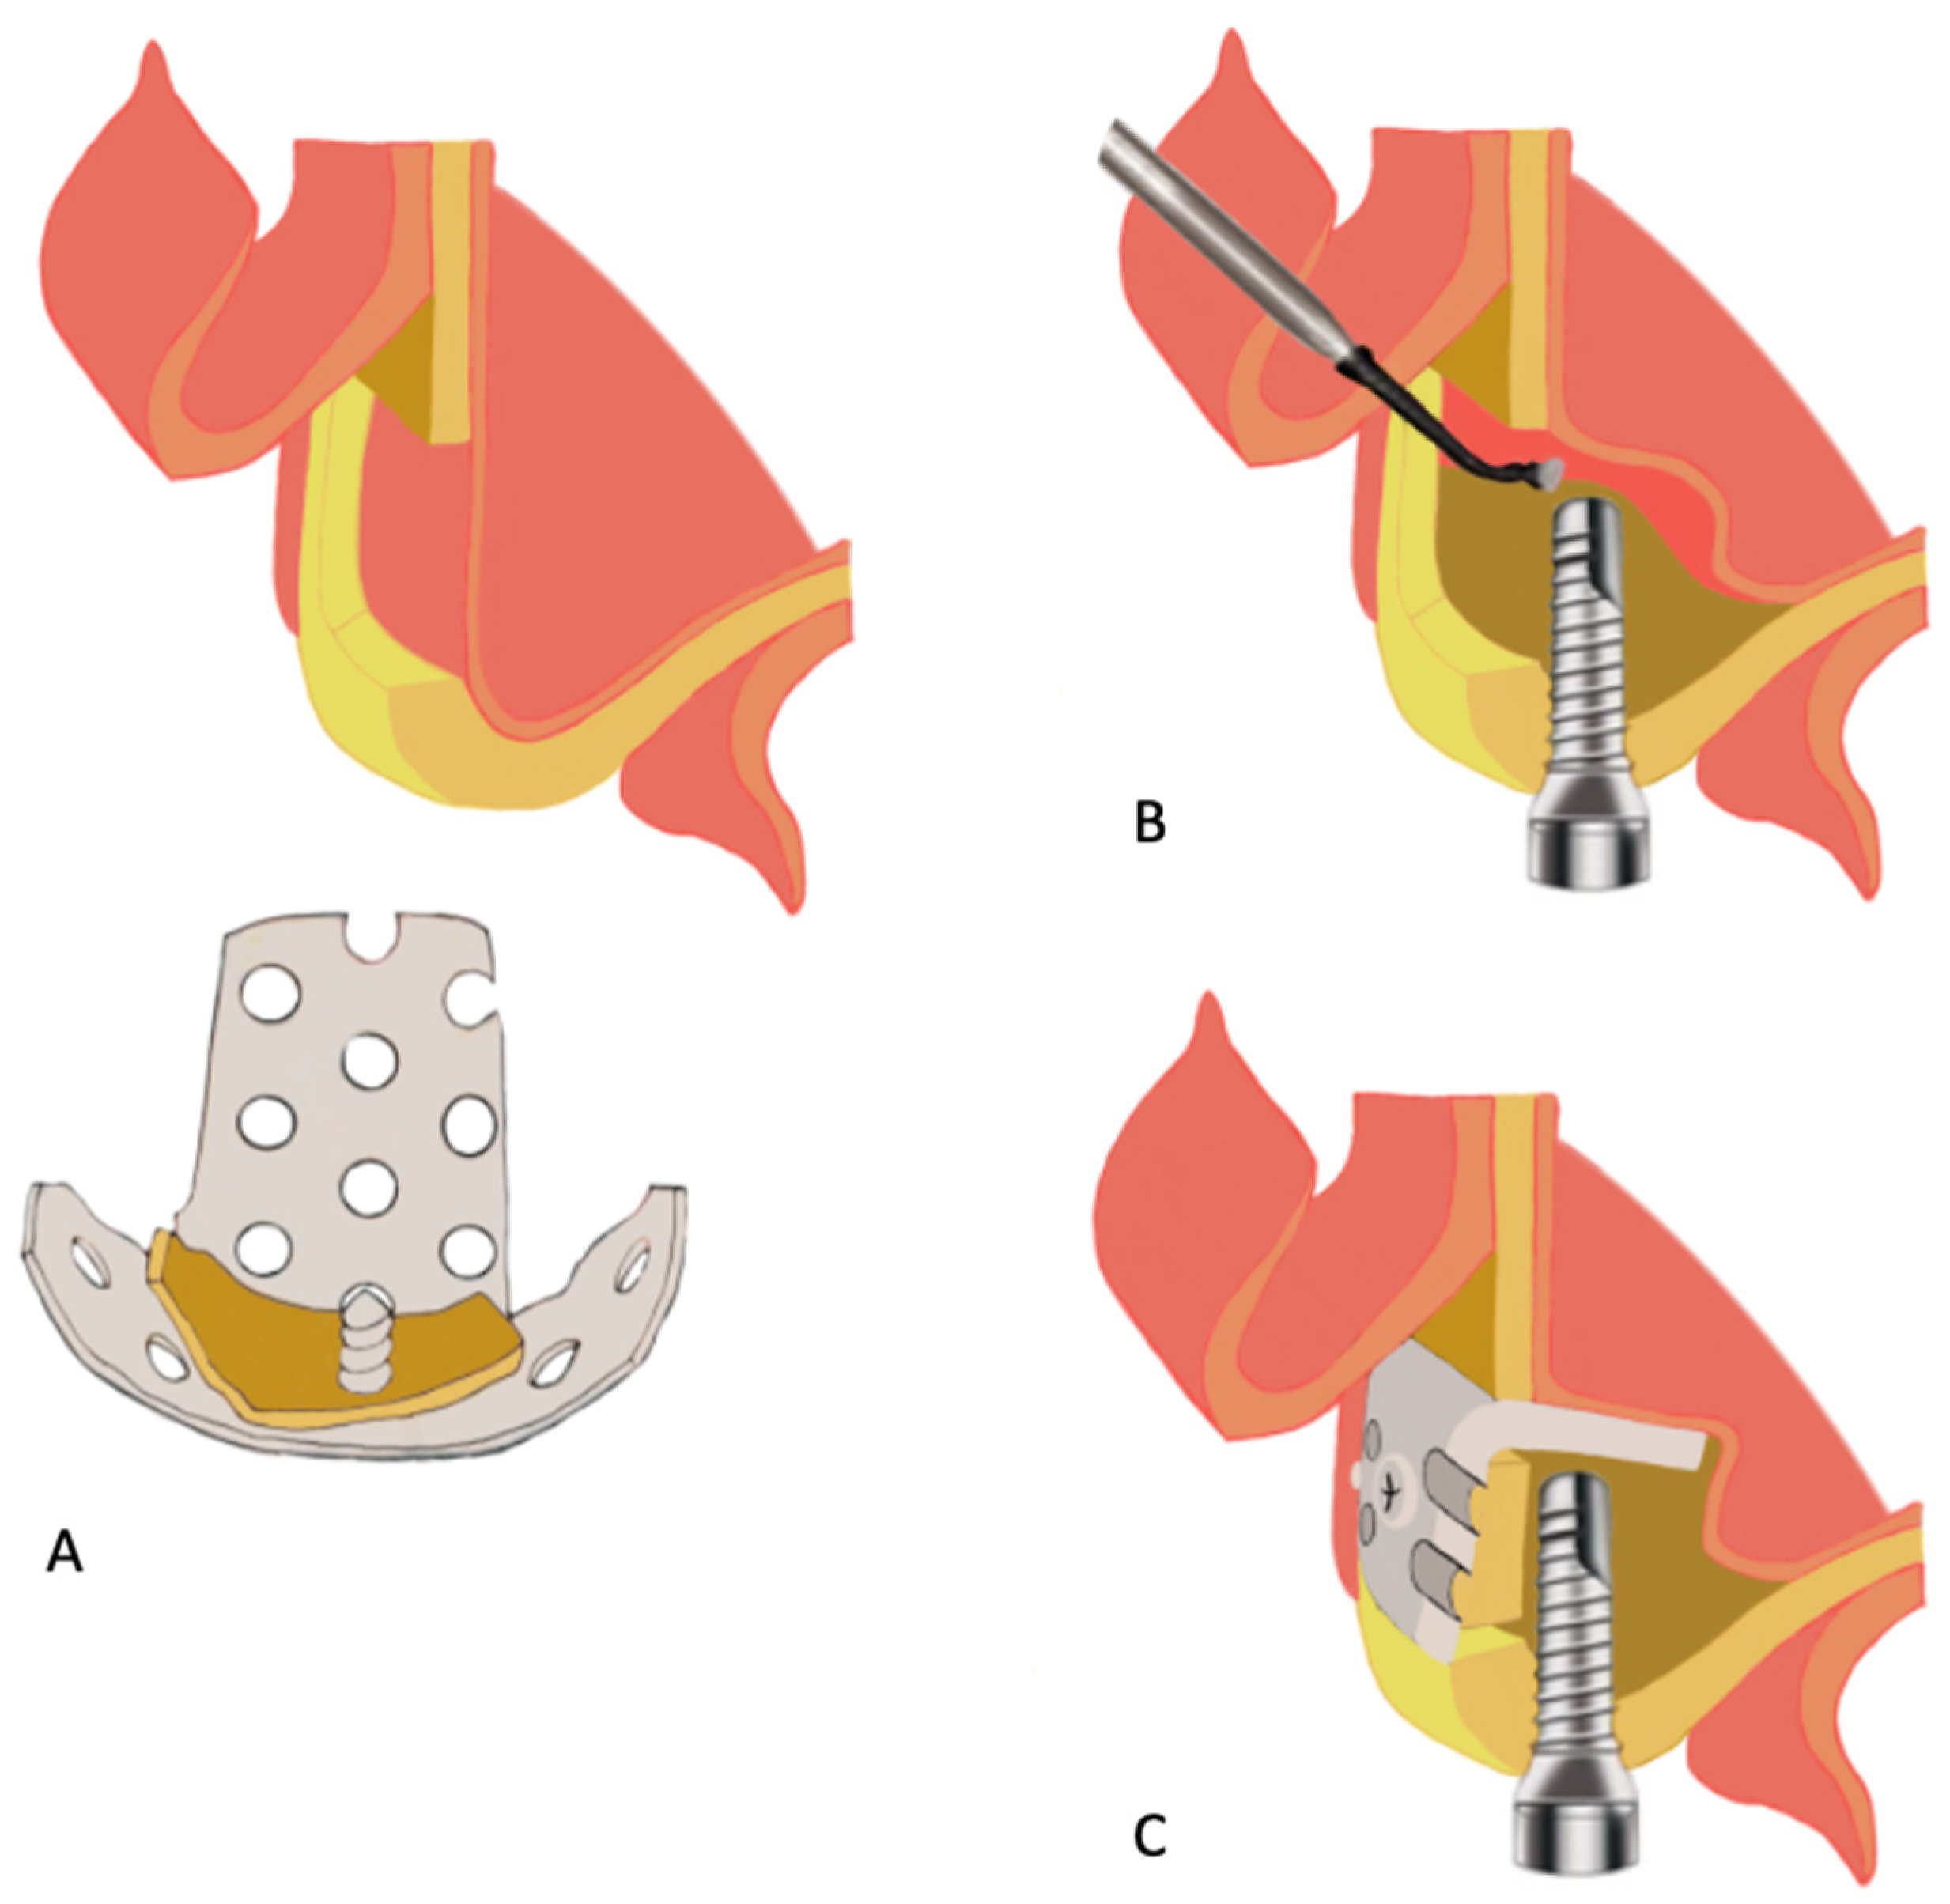

- Sukegawa, S.; Kawai, H.; Nakano, K.; Takabatake, K.; Kanno, T.; Nagatsuka, H.; Furuki, Y. Advantage of Alveolar Ridge Augmentation with Bioactive/Bioresorbable Screws Made of Composites of Unsintered Hydroxyapatite and Poly-L-lactide. Materials 2019, 12, 3681. [Google Scholar] [CrossRef] [Green Version]